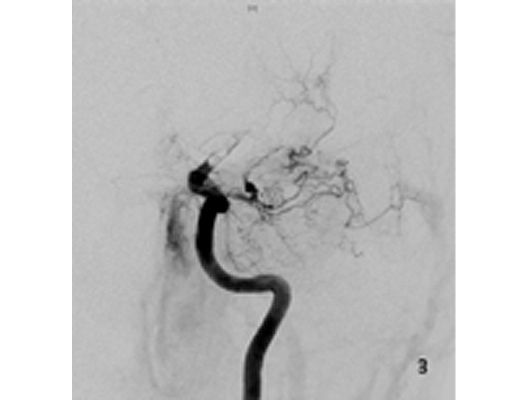

Mit den modernen Verfahren zur Wiedereröffnung von verschlossenen Blutgefäßen können wir Patienten mit Schlaganfall in vielen Fällen helfen. Das folgende Beispiel zeigt die angiographischen Bilder eines Patienten, der mit vollständiger Lähmung der rechten Körperhälfte und einer schweren Sprachstörung eingeliefert wurde. Ursächlich zeigte sich ein Verschluss der linken Halsschlagader, vermutlich auf dem Boden einer arteriosklerotischen Einengung (Bild 1). Das Gefäß wurde daraufhin mit einem Stent wiedereröffnet (Bild 2). Zusätzlich zeigte sich ein Verschluss der Endstrecke des Gefäßes durch Blutgerinnsel (Bild 3). Diese konnten vollständig entfernt werden (Bild 4). Der Patient erholte sich nach der Behandlung innerhalb weniger Tage vollständig.